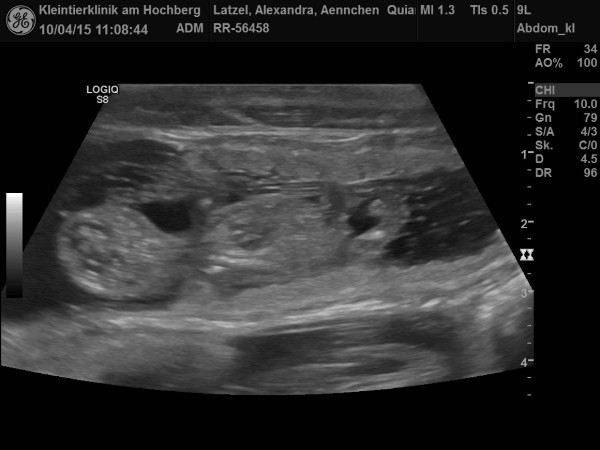

| Quiana von Waltenweiler genannt Ännchen ist Schwanger! Hier seht ihr die Ultraschallbilder |